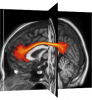

UManitoba-JHU Functionally-Defined Human White Matter Atlas

This is a probabilistic atlas of human white matter tracts/regions underlying several well-known resting state brain networks (e.g., dorsal and ventral Default Mode, left and right Executive Control, anterior and posterior Salience, Basal Ganglia, Language, Sensorimotor, Visuospatial, etc.). These were derived by performing fMRI-guided DTI tractography on a group of 32 neurologically-healthy, adult control subjects. The atlas includes group probability maps for each network, as well as each individual tract (i.e., 1-mm isotropic NIFTI images) that are aligned to both the SPM and MRIStudio ICBM templates. In accordance with the CC BY-NC-ND 4.0 License, this atlas may be used for academic purposes, but users should cite the following two papers: